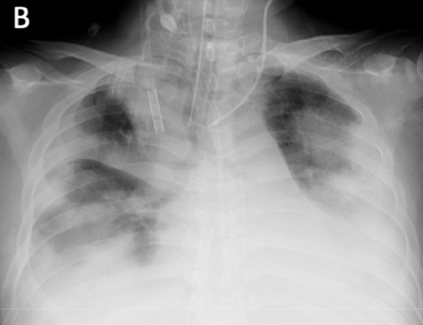

Across the world's coronavirus disease 2019 (COVID-19) hot spots, the need to streamline patient diagnosis and management has become more pressing than ever. As one of the main imaging tools, chest X-rays (CXRs) are common, fast, non-invasive, relatively cheap, and potentially bedside to monitor the progression of the disease. This paper describes the first public COVID-19 image data collection as well as a preliminary exploration of possible use cases for the data. This dataset currently contains hundreds of frontal view X-rays and is the largest public resource for COVID-19 image and prognostic data, making it a necessary resource to develop and evaluate tools to aid in the treatment of COVID-19. It was manually aggregated from publication figures as well as various web based repositories into a machine learning (ML) friendly format with accompanying dataloader code. We collected frontal and lateral view imagery and metadata such as the time since first symptoms, intensive care unit (ICU) status, survival status, intubation status, or hospital location. We present multiple possible use cases for the data such as predicting the need for the ICU, predicting patient survival, and understanding a patient's trajectory during treatment. Data can be accessed here: https://github.com/ieee8023/covid-chestxray-dataset